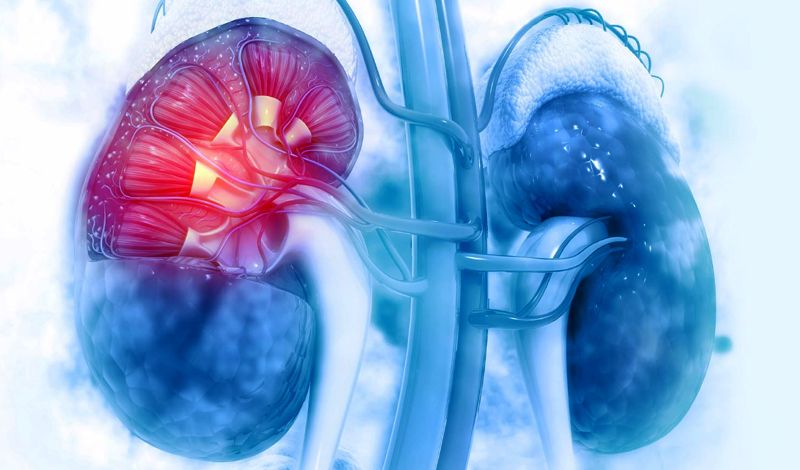

Acute Kidney Injury

Acute Kidney Injury (AKI), also known as acute renal failure, is a sudden decline in kidney function that

Chronic Kidney Disease

Chronic Kidney Disease (CKD) is a long-term condition in which the kidneys gradually lose their ability